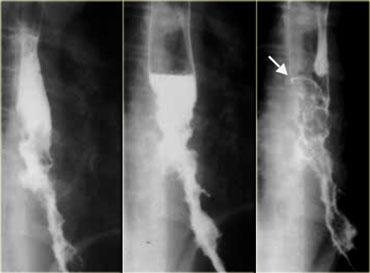

Các hình ảnh này của một bệnh nhân có ung thư dạng giãn tĩnh mạch.

Hình ảnh các khuyết thuốc không thay đổi gợi ý đây là khối u hơn là giãn tĩnh mạch thực sự.

Lưu ý bờ trên sắc nét của tổn thương và ổ loét (mũi tên)

Ngoài cùng bên trái là hình ảnh của một bệnh nhân có ung thư dạng giãn tĩnh mạch.

Các thùy dài mô phỏng hình ảnh giãn tĩnh mạch nhưng không thay đổi trong quá trình soi huỳnh quang.

Lưu ý các nếp niêm mạc không đều, lớn và khối mô mềm (mũi tên) ở đáy vị

Kế bên là hình ảnh của một bệnh nhân có ung thư lan tràn bề mặt.

Tổn thương lan tràn bề mặt rộng liên quan đến đoạn thực quản xa.

Hình ảnh này có thể gặp ở cả tổn thương sớm lẫn tổn thương tiến triển.